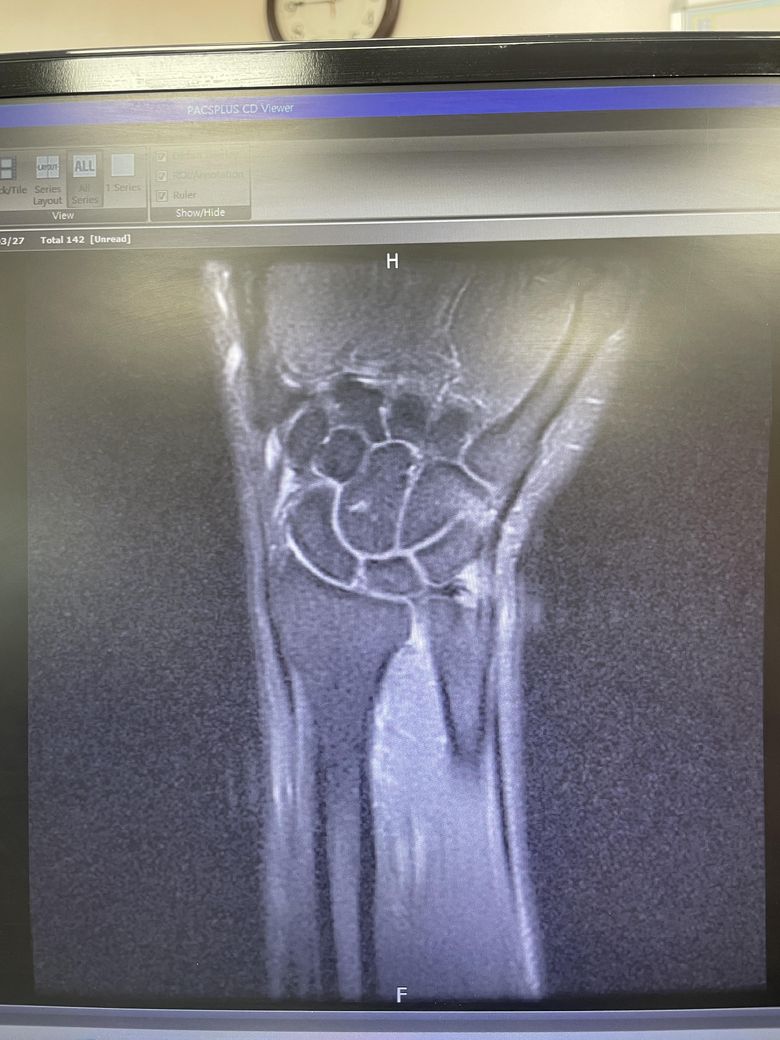

tfcc 파열진단 받았습니다. MRI 판독좀 부탁드립니다.

1A 1B 1C 중 어디에 해당하는지 알고 싶고

파열정도가 심한건지 궁금합니다.

아니면 보존적 치료(주사)로 괜찮은지.. 관절경 봉합술을 해야하는지..

MRI상 TFCC 부위에 고강도 신호가 보이고 파열이 의심됩니다. 통증이 40일 이상 지속되고 있어 보존치료 효과가 낮을 수 있습니다.

관절경 수술로 손상부위를 봉합하면 회복과 재발 방지에 도움이 됩니다. 스포츠 손상 전문 정형외과에서 수술 여부를 재평가받는 것이 좋습니다!